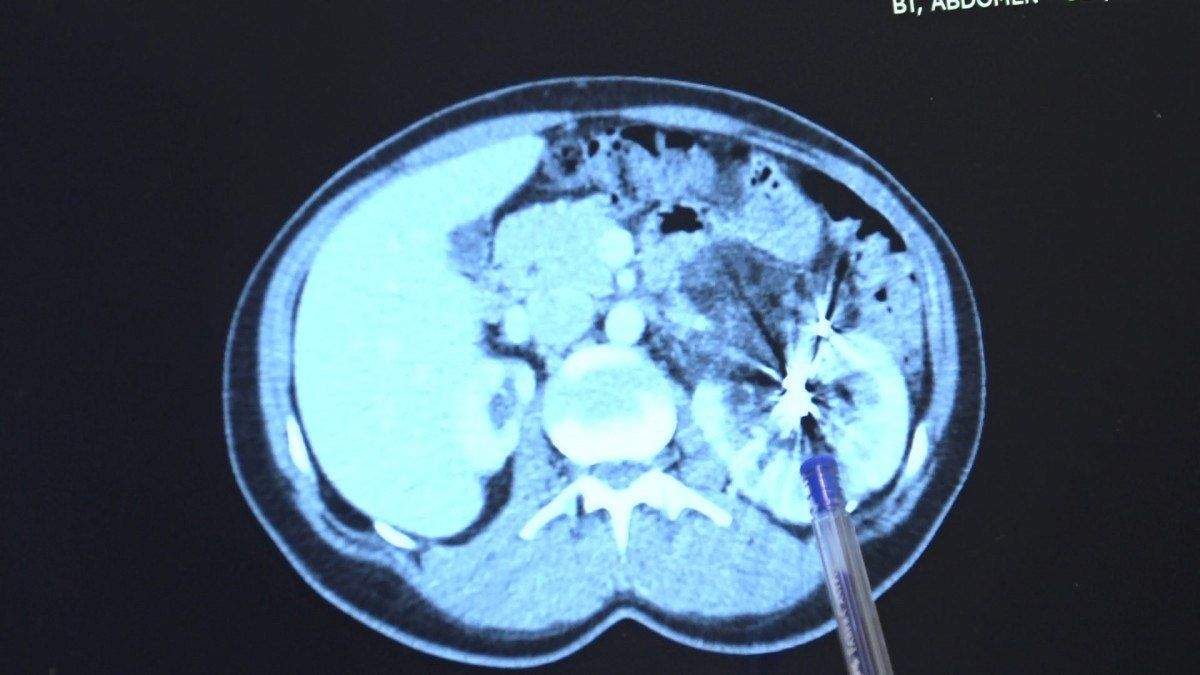

Yıllar sonra tekrar MR çektiren hastanın tek böbreğinde bu sefer bir kitle olduğu görüldü.

Zorlu bir ameliyatı başarıyla tamamlayan Bursa Medicana Hastanesi Üroloji Uzmanı Doç. Dr. Ahmet Şahan, hastanın durumunun şuan iyi olduğunu belirterek, “Nurcan Hanım 35 yaşında bize İzmir’den geldi. Doğuştan tek böbrekli bir böbreği küçük olduğu için işlevsiz durumda. Sağlam böbreğinde ise 2016’da tanısı konmuş giderek büyüyen iyi huylu “anjiomyolipomu” denilen 12 santimetre boyutunda bir kitlesi var.

Bu kitle artık böbreğin damarlarını içerisine almış komplike bir kitle durumunda. Hastaya iki kez anjioembolizasyon tedavisi uygulanmış fakat başarısız olduğu için kitle büyümeye devam etmiş. Kadınlarda 4 santimetreden büyük anjiomyolipomular kendiliğinden kanayarak yaşamı tehlike altına attığı için bu kitlelerin alınması gerekiyor.